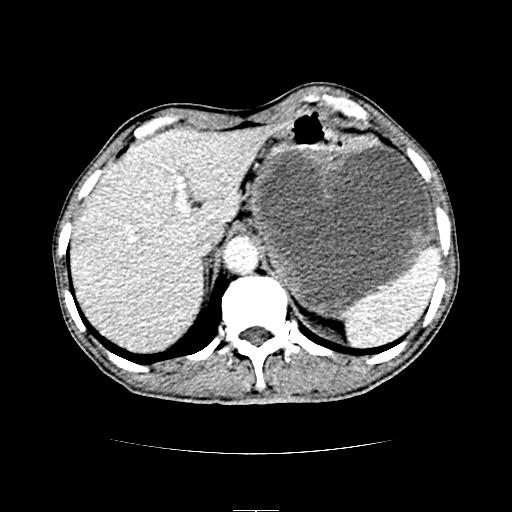

胰尾部巨大囊性病变,胰腺体积增大.左肾吉氏筋膜增厚.1慢性胰腺炎伴随假性囊肿2左肾囊肿

左上腹胃、脾及胰腺间巨大囊性占位性病变,内见多数薄隔,有轻度强化,明显占位效应。左肾见一小囊肿。

考虑:1、左上腹巨大囊肿(可能来源于胰腺)。

左上腹胃、脾及胰腺间巨大囊性占位性病变,内见多数薄隔,有轻度强化,明显占位效应,胰腺及左肾结构清楚,明显向后下方推压 移位。左肾见一小囊肿.多考虑:1 网膜巨大囊肿。2 左肾小囊肿。

1胃脾胰之间一巨大囊性影,胃明显向前推移,胰体尾部似肥大,考虑囊性影来源于胰腺(假性囊肿?)2左肾小囊肿。

左上腹囊性占位,虽与胰腺分界不清,胰尾似乎受压前移,病灶最大截面并不在胰腺水平,考虑来源于网膜可能性大吧,应再详细追问病史.